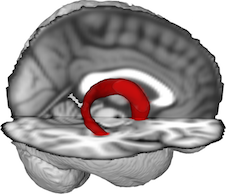

Fornix FMRIB FA 1mm Template

A merged, younger-older adult template that covers the majority of the fornix from the hippocampal formation to septal and diencephalic regions. Generated from probabilistic tractography pathways of the fornix in 49 younger adults (mean age = 32.5, range = 25–40, M:25, F:24) and 46 older adults (mean age = 65.3, range = 60–77, M:26, F:20). Kindly provided by Brian Gold.

The tractography pathways of all participants were registered to FMRIB58_FA standard-space and averaged. The template was shown to be a sensitive tool for comparisons between older and younger adults.

- Brown CA, Johnson NF, Anderson-Mooney AJ, Jicha GA, Shaw LM Trojanowski JQ, Van Eldik LJ, Schmitt FA, Smith CD, & Gold BT (2017). Development, validation and application of a new fornix template for studies of aging and preclinical Alzheimer’s disease. NeuroImage: Clinical, 13; 106-115.